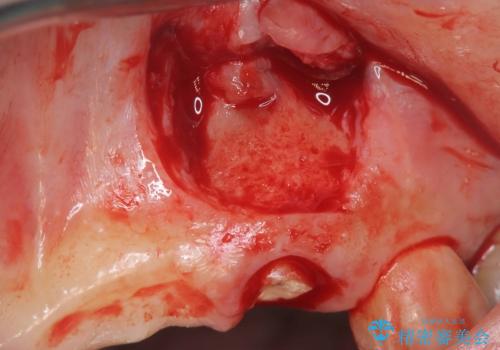

術前のCT画像より、抜歯即時インプラントが可能と判断したため、抜歯と同時にインプラント埋入を行いました。術式にはセミルーナーフラップを用い、唇側の骨吸収を抑える目的でルートメンブレンテクニックを併用しました。

抜歯即時インプラントには、切開量が少なく痛みが出にくいこと、一度の手術で治療が完了するため治療期間を短くでき、患者様の身体的負担も軽減できるという大きなメリットがあります。

今回のケースでも、しっかりと固定が得られたため、手術は1回で終了し、短期間でオールセラミッククラウンまで装着することができました。患者様も術後の痛みはなく、処方した痛み止めも服用されなかったとのことです。